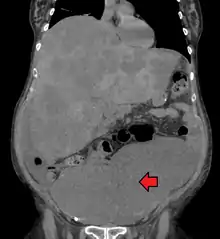

![]() | |

| Location and appearance of two example colorectal tumors | |